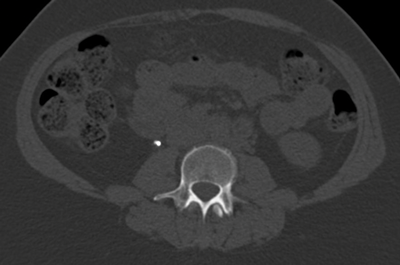

Figure 2a: Abdominal windows stone with contrast.

Figure 2b: Bone windows stone with contrast.

CT urograms can be performed with a pre-contrast CTKUB to assess for stone disease and calcification, but some centres only perform a post-contrast urographic phase in order to decrease radiation dose. Newer dual-energy CT scanners include software that enables a ‘virtual pre-contrast CT’ to be reconstructed by a subtraction technique. Using bone windows enables some calculi to be visualised even in the presence of contrast in the collecting systems due to the different HU values of contrast and calculi (Figure 2). However, it can be difficult to clearly depict some calculi using abdominal windows in this group of patients as the stone will be masked by the excreted contrast.